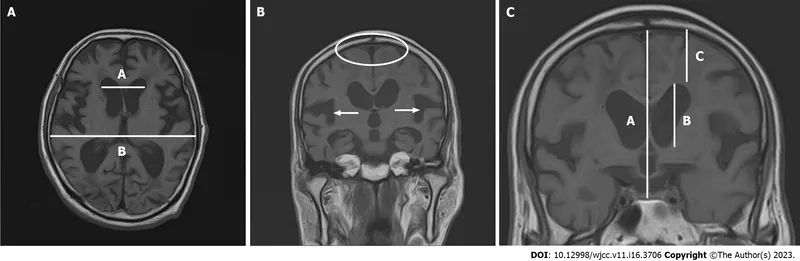

Understanding hydrocephalus in adults